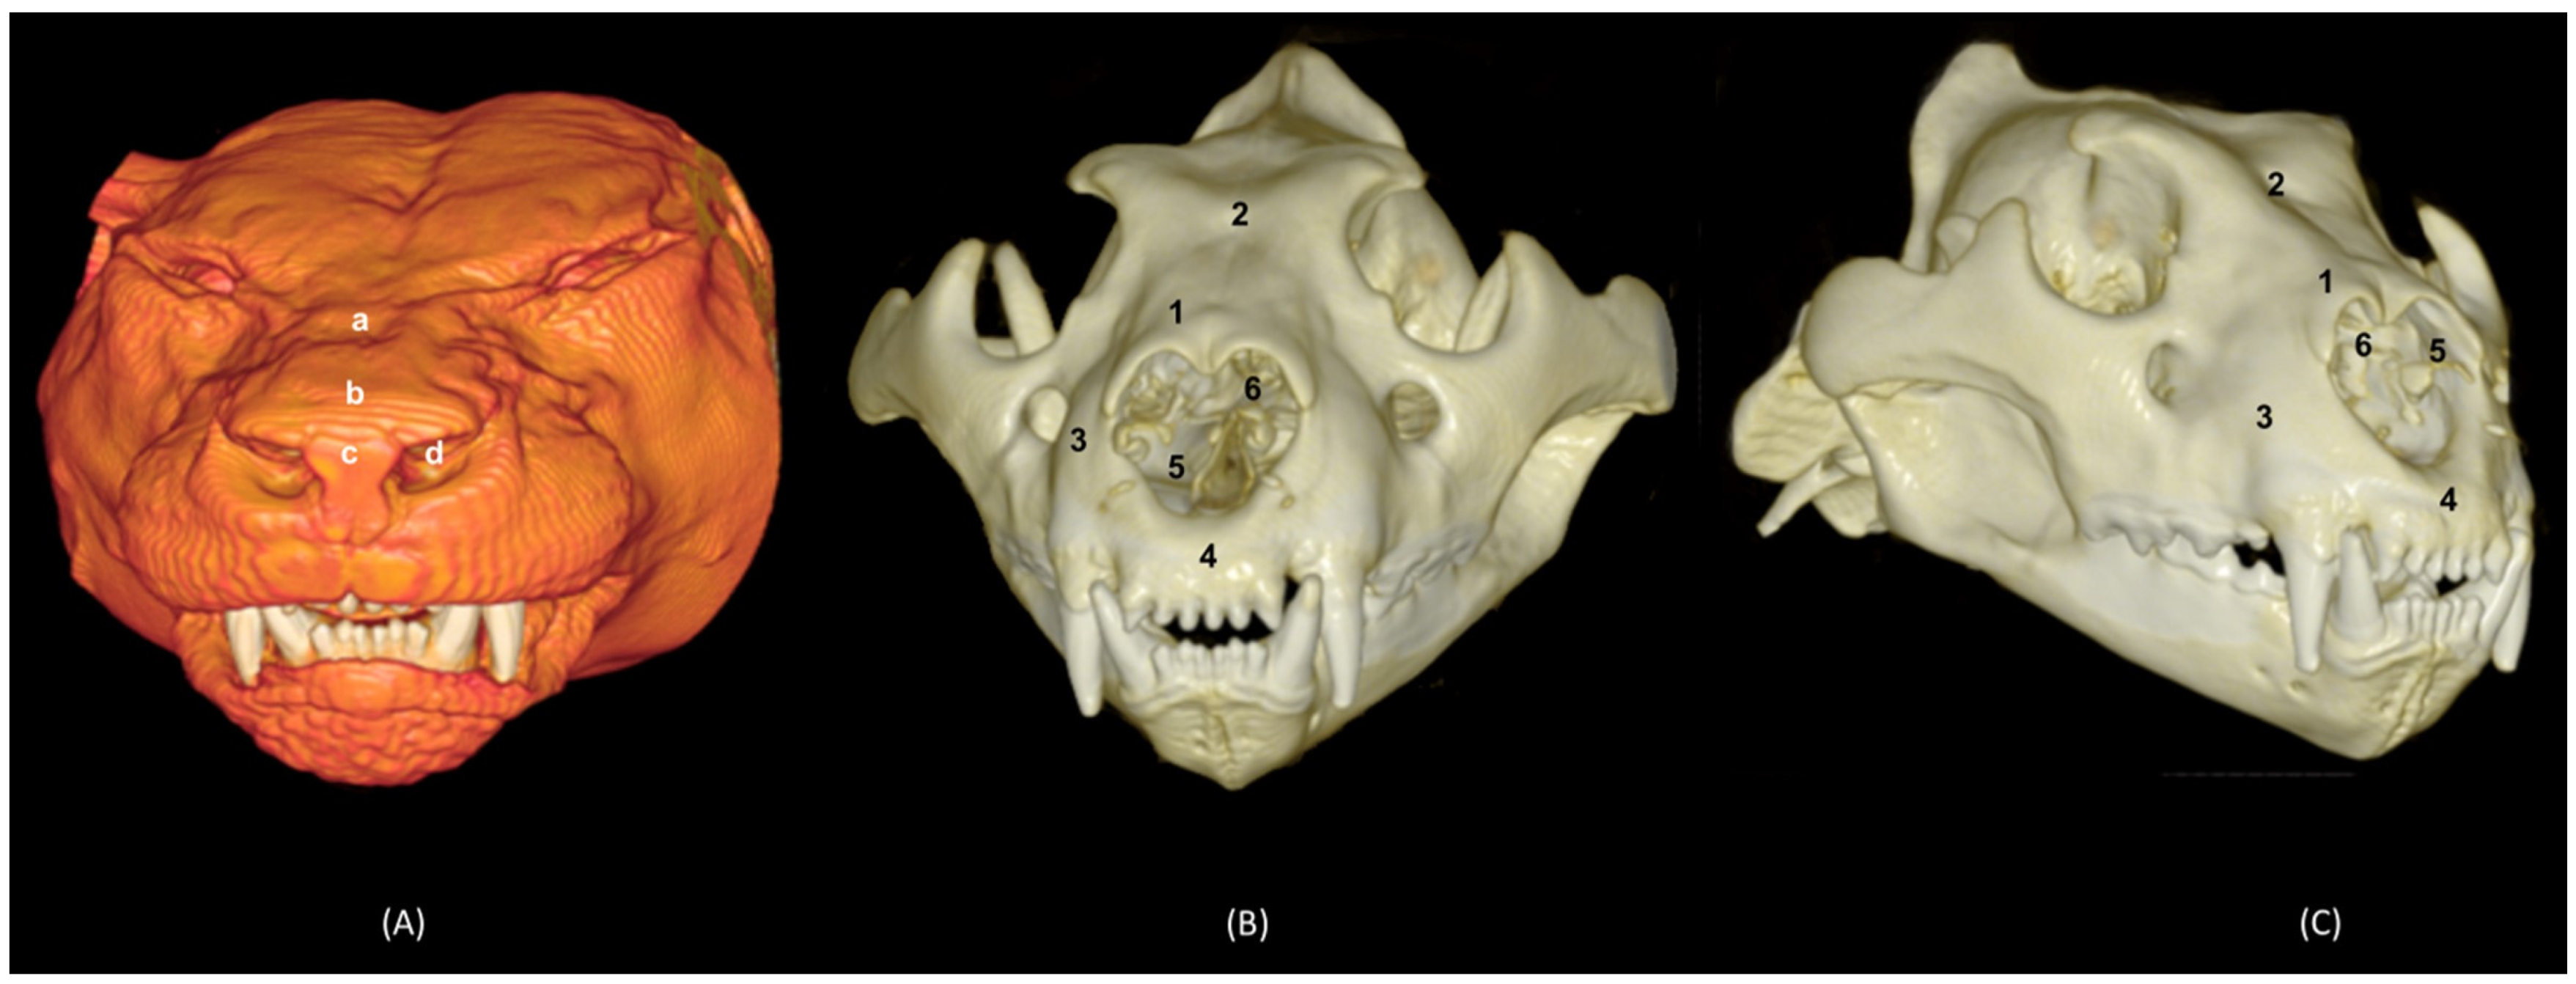

In addition, four OsiriX surface and deep VR reconstruction CT images of the felid’s heads are presented (Figure 31, Figure 32, Figure 33 and Figure 34). These VR images allowed for the assessment of the external nose and the integrity and the extensions of the bones, enhancing the anatomical understanding of this region.

Figure 31 shows the reconstructed leopard images. The nasal plane and the bony framework that supports the nasal cavity were clearly observed, as well as the boundaries between these bones. In this way, we visualized the frontal and the nasal bones, laterally the maxilla and ventrally the most rostral side of the incisive bone.

Figure 31. OsiriX 3D reconstructed CT images of the leopard’s head showing the external nares and nasal plane. (A): VR surface reconstruction. Rostral view. (B): VR deep reconstruction. Rostral view. (C) VR deep reconstruction. Right rostrolateral view. a. Root of the nose; b. Dorsum of the nose; c. Tip of the nose; d. Nasal orifice; 1. Nasal bone; 2. Frontal bone; 3. Maxilla; 4. Incisive bone; 5. Nasal cavity; 6. Turbinates.

In the lion CT VR images (Figure 32), we could also observe the external nose and these bones. However, the morphology of these skulls differed from the rest. The short rostral extension of the nasal bone was observed, as well as the convex morphology that the frontal bone acquires. The bone structure was much more compact than in other felines.

Figure 32. OsiriX 3D reconstructed CT images of the lion’s head showing the external nares and nasal plane. (A): VR surface reconstruction. Rostral view. (B): VR deep reconstruction. Rostral view. (C) VR deep reconstruction. Right rostrolateral view. a. Root of the nose; b. Dorsum of the nose; c. Tip of the nose; d. Nasal orifice; 1. Nasal bone; 2. Frontal bone; 3. Maxilla; 4. Incisive bone; 5. Nasal cavity; 6. Turbinates.

In the reconstruction of the cheetah’s head (Figure 33), the limit between the frontal and nasal bones was not so pronounced. The frontal bone in the cheetah was completely concave, unlike the lion.

Figure 33. OsiriX 3D reconstructed CT images of the cheetah’s head showing the external nares and nasal plane. (A): VR surface reconstruction. Rostral view. (B): VR deep reconstruction. Rostral view. (C) VR deep reconstruction. Right rostrolateral view. a. Root of the nose; b. Dorsum of the nose; c. Tip of the nose; d. Nasal orifice; 1. Nasal bone; 2. Frontal bone; 3. Maxilla; 4. Incisive bone; 5. Nasal cavity; 6. Turbinates.

Finally, the VR reconstruction of the domestic cat skull (Figure 34) showed that the bone limits were not as noticeable as in the leopard or cheetah. The frontal bone represents a large extension since its zygomatic process developed very laterally, unlike in big felids.

Figure 34. OsiriX 3D reconstructed CT images of the cat’s head showing the external nares and nasal plane. (A): VR surface reconstruction. Rostral view. (B): VR deep reconstruction. Rostral view. (C) VR deep reconstruction. Right rostrolateral view. a. Root of the nose; b. Dorsum of the nose; c. Tip of the nose; d. Nasal orifice; 1. Nasal bone; 2. Frontal bone; 3. Maxilla; 4. Incisive bone; 5. Nasal cavity; 6. Turbinates.